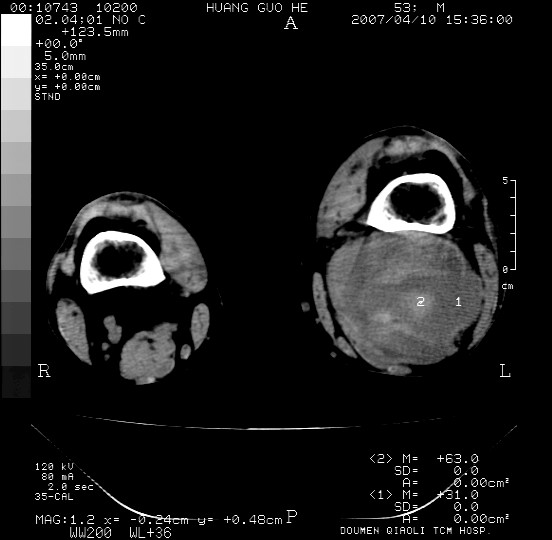

男性,左腘窝包块五个月,逐渐增大,疼痛功能受限,无发热。

查:远端血供差,质地硬。

左侧膝关节后国窝处略低密度软组织肿块,边界清楚,内见脂肪密度及高密度影.多考虑:软组织肿瘤_首选:脂肪纤维瘤.

考虑左腘窝囊性病变伴出血。

左侧腘窝软组织肿块,边缘清晰,其内密度不均,周围骨组织无破坏,病灶增长较快,考虑:恶性病变(腘窝滑膜肉瘤可能),建议穿刺活检。